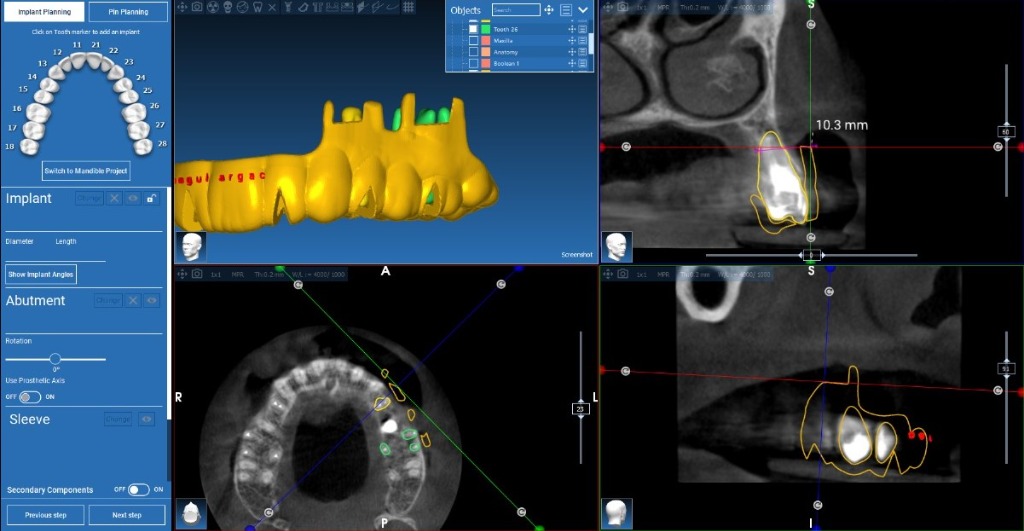

Maxillary Implant Case — 3 Implants

Tooth-supported guide for 3 implants in the upper jaw. Digital planning with precise implant positioning.